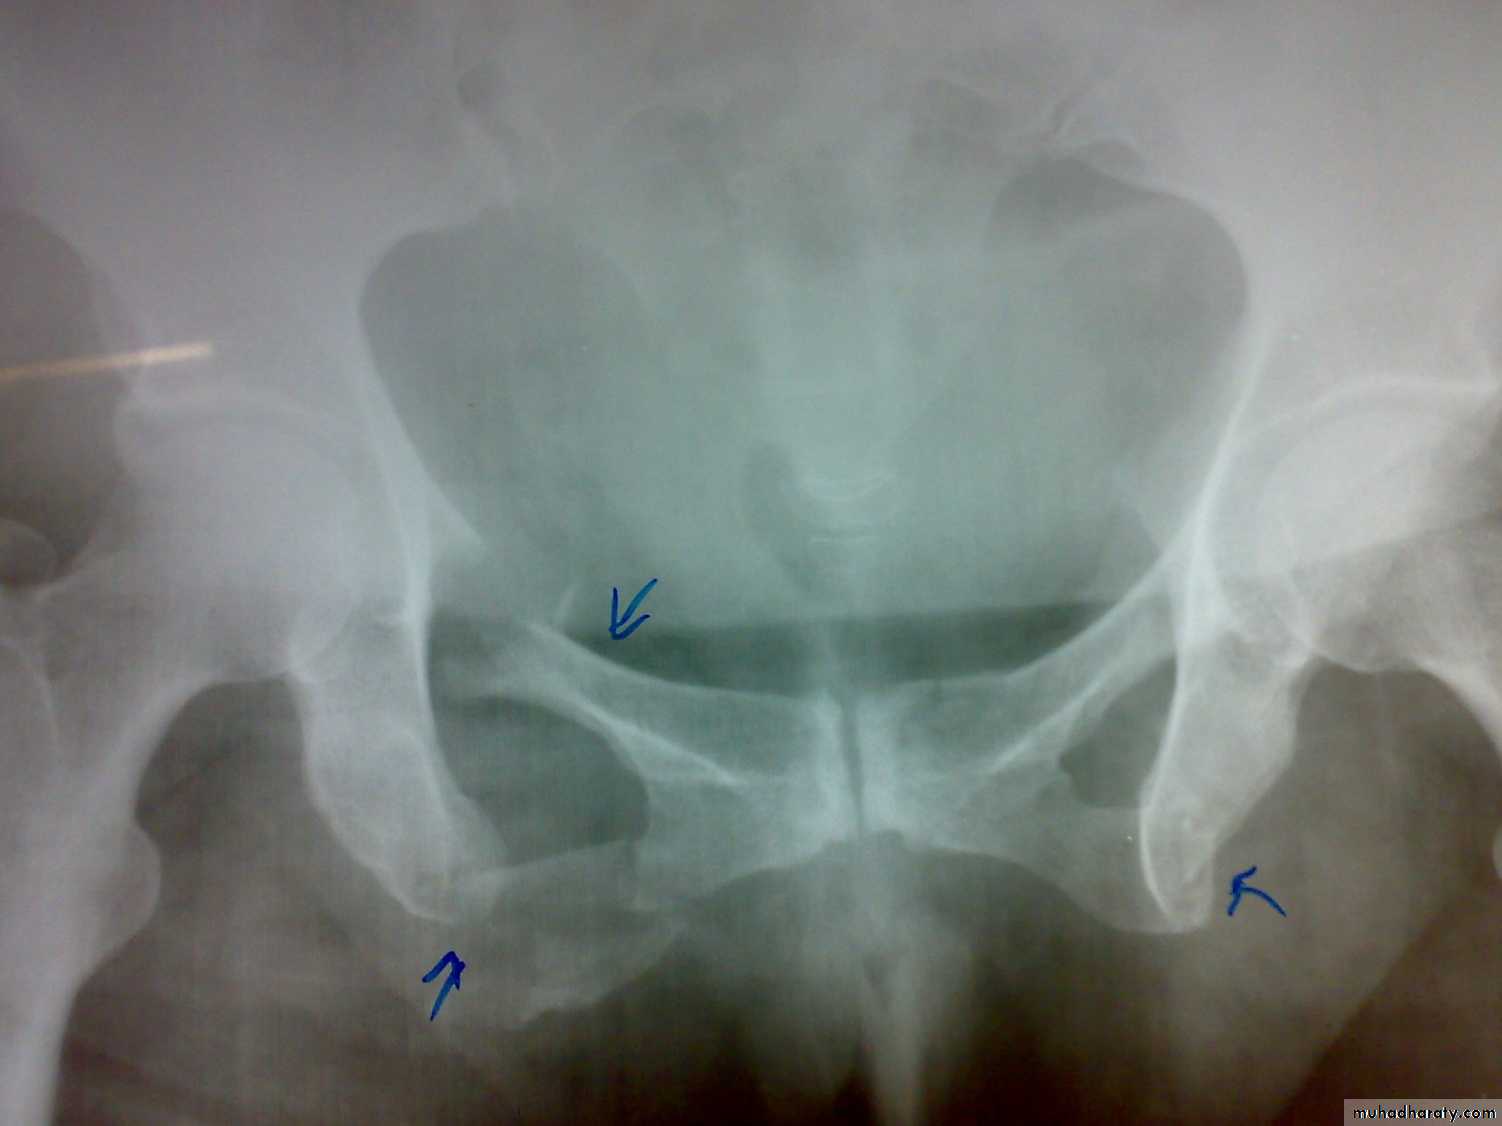

1- antero-posterior compression (open book).

X- ray: Ideally five views should be obtained : Standard anteroposterior view, inlet view, outlet view, right oblique view, and left oblique view, but x-ray shouldn't be done until the patient become stable .

Severe bleeding is the main cause of death following high-energy pelvic fractures. If there is an unstable fracture of the pelvis, hemorrhage will be reduced by rapidly applying a pelvic binder or an external fixator.

Treatment of the fracture

Open book injuries with a gap of less than 2cm at the symphisis pubis can be treated with bed rest for 6 weeks. If the gap is more than 2cm, external fixator with pins in the iliac blades and anterior bar may be used for 8-12 weeks. The other option is anterior plating.Severe vertical shear and compression injuries are the most dangerous and most difficult to treat. The fracture or dislocation must be stabilized by external fixation or posterior iliosacral screw or anterior plating with posterior iliosacral screw . Vertical force fractures may be treated by open reduction and internal fixation or skeletal traction and non weight bearing for 3 months